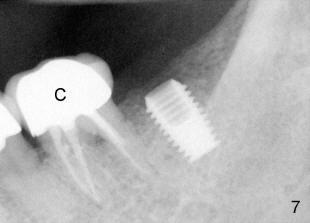

Fifty-four year old lady had had discomfort with a cantilever bridge (FPD) that restored #18 (Fig.1) and agreed to have FPD removed (Fig.2) and place implant (Fig.3: 5x8) 22 months ago. The lingual plateau of the implant was exposed due to plate perforation (Fig.4: <). At implant placement, #19 was found to have recurrent apical periodontitis. This tooth had root canal retreatment (Fig.5: 19), build-up (Fig.6: B) and crown (Fig.7: C).

Black healing plug was found exposed 1 week after implant placement: Fig.5 was taken 2 months post-op; the tissue around the plug looks healthy (<). Fig.7 X-ray was taken immediately before uncover, 3 months post-implant: there is crest bone resorption, as compared to Fig.3. The lingual plateau is not covered by bone (Fig.6: uncover).

A 4x6.5 non-shouldered abutment was inserted, prep and impressed for PFM on uncover. Fig. 8 PA was taken after intraoral cementation of crown (C).